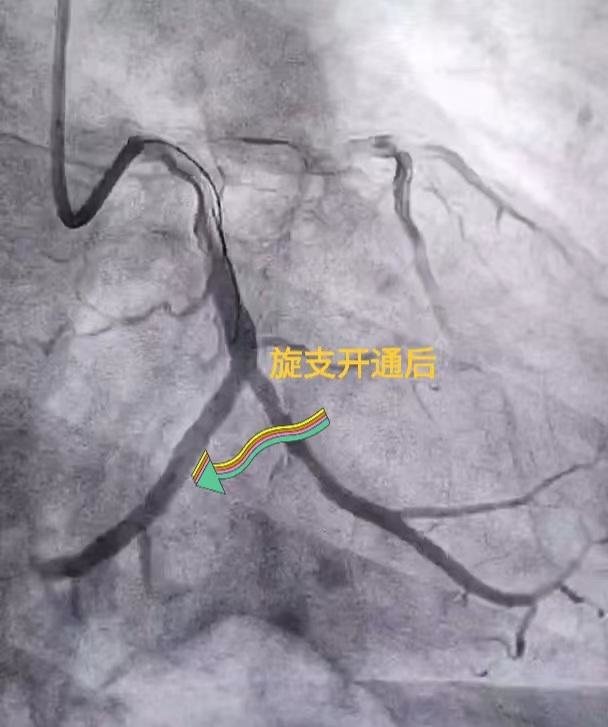

等张先生到达医院后,心血管内科李超民副主任团队为患者进行急诊冠脉造影,结果诊断为巨大的左旋支闭塞。医生立刻开通闭塞旋支,进行经皮冠状动脉腔内成形术。术后患者胸痛症状消失,房颤转为正常窦性心律。

李超民副主任介绍,急性心肌梗死的救治原则是尽量缩短心肌的救治时间,也就是说时间就是心肌,时间就是生命。介入微创开通闭塞的心脏血管是目前最有效的治疗方法。在各科室的全力配合下,用时不到一小时就为患者开通了闭塞的血管,减少心肌坏死,降低了心肌梗死的并发症,挽救了患者的生命。目前是心脑血管疾病的高发季节,希望广大市民重视胸痛的发作,一旦有类似情况发生,请拨打120尽快到医院急诊科就诊。